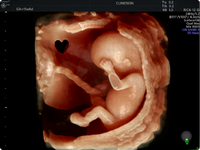

Ultrassom de Ginecologia e

Obstetrícia

Equipamentos de ponta e metodologias inovadoras para o acompanhamento materno-fetal nos diferentes estágios da gestação. Aqui você encontra um atendimento diferenciado e acolhedor nos exames obstétricos, com telão e projetor na sala para melhor visualização do bebê.